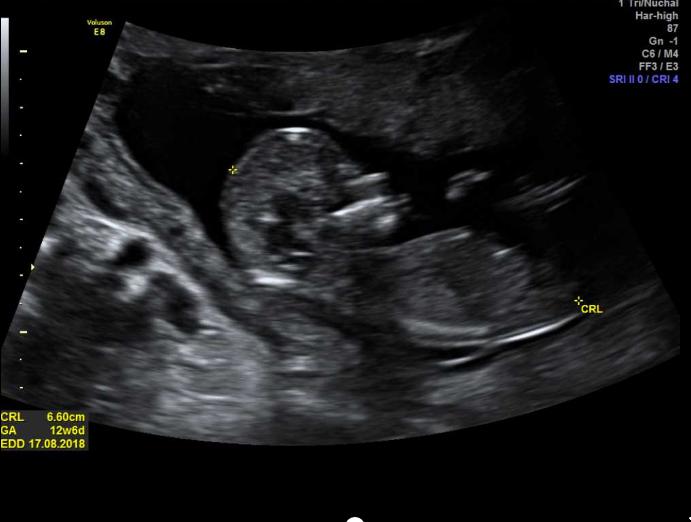

I had my 12 weeks 6 day scan and I'm not sure if i see a nub, any guesses on the gender?

Girl lean based on second pic from the botttom but none of the pics really show the nub clear enough for me to be super confident.

I’m thinking girl, but not really good at guessing!

I am guessing girl based on the 5th pic.

Congratulations on your pregnancy Pink! Girl guess from me especially the second last pic! Have you posted your second sway?